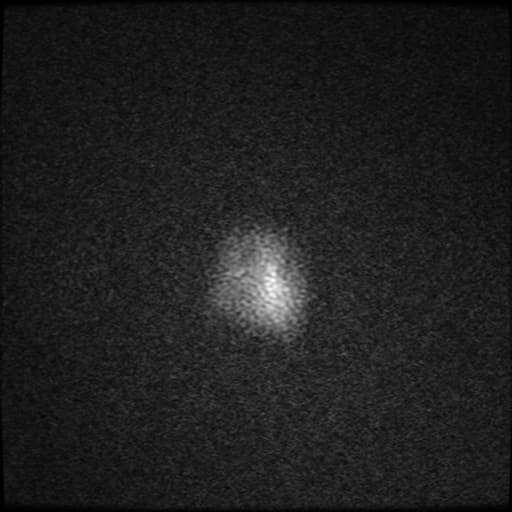

DWI/ADC

tín hiệu DWI cao thường hiện diện ở trung tâm 11

biểu hiện cho hạn chế khuếch tán thực sự

hạn chế khuếch tán ở vùng ngoại vi hoặc rải rác cũng có thể thấy; tuy nhiên, phát hiện này không phải lúc nào cũng ổn định, với đến một nửa các tổn thương viền ngấm thuốc có một phần hạn chế khuếch tán nhưng không phải là áp xe

trong một số trường hợp suy giảm miễn dịch, nội dung trung tâm có thể không hạn chế khuếch tán (ví dụ: lao, toxoplasmosis não) 13